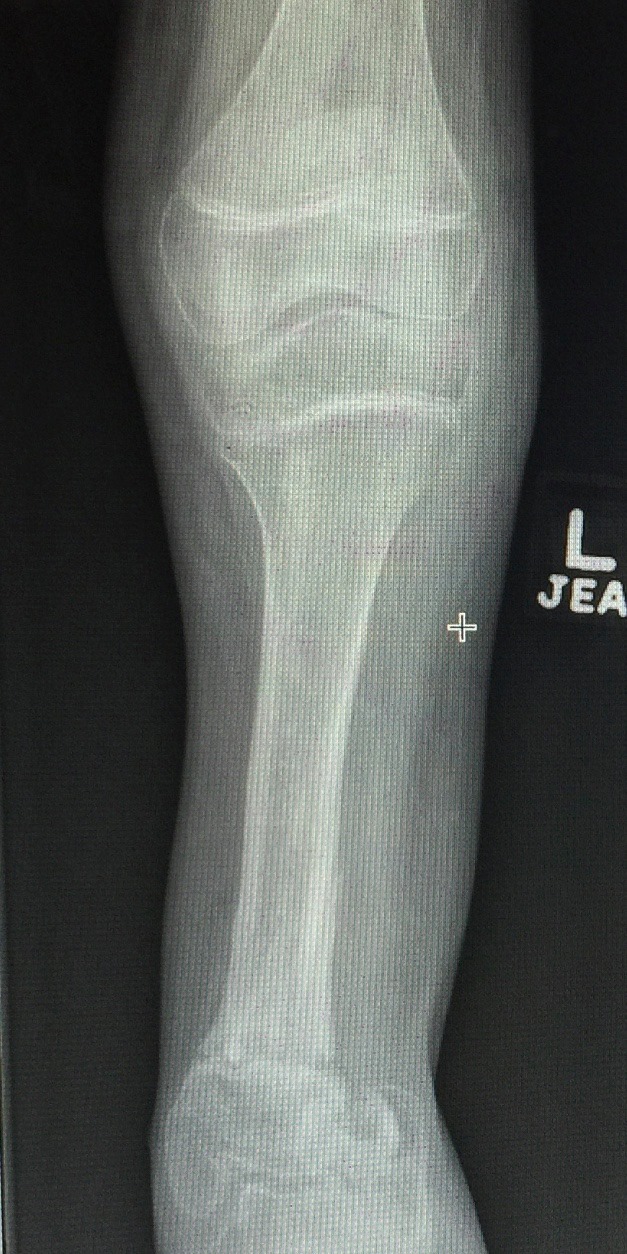

Ausencia congenita del peroné

A los papás de Lazarito les dijeron en Estados Unidos que la única alternativa para su hijo era una amputación; buscando segundas opiniones, llegaron conmigo. Lazarito, de 13 años, tiene #hemimelia #perónea, una ausencia congénita del peroné que causa malformaciones y acortamientos. Para evitar la amputación, se le realizó una reconstrucción del tobillo y alineamos su pierna de forma funcional. Ahora, mi pacientito ya camina con apoyo al 100%, realiza sus actividades diarias y dice que empezará a jugar fútbol. Agradezco a sus papás por la confianza y a sus familiares en Guadalajara por recomendarlo conmigo.